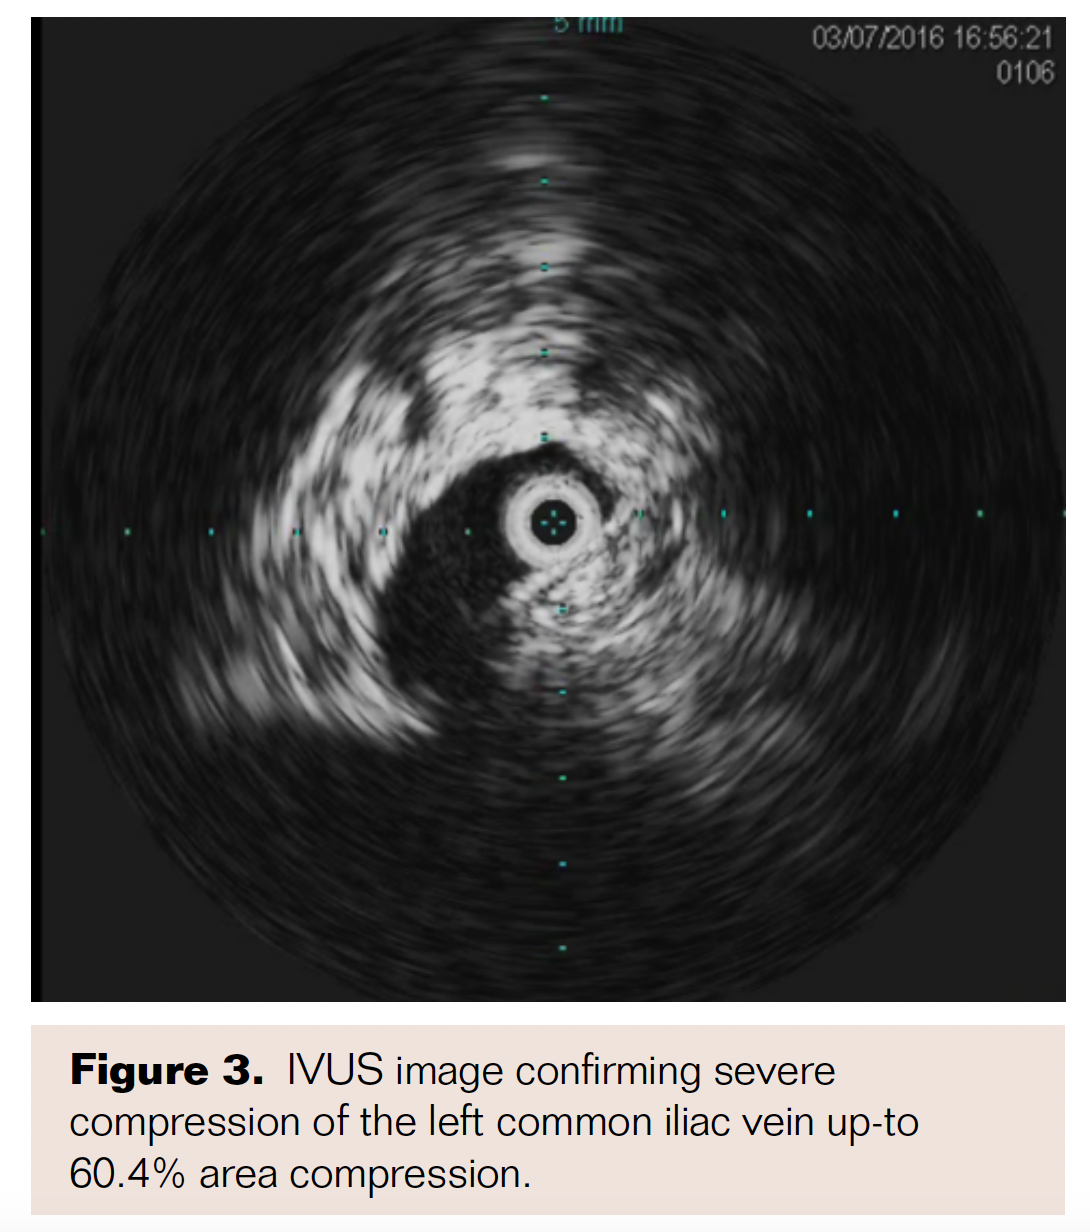

Selective left lower-extremity venography was performed with the patient placed in supine frog-legged position and ultrasound-guided 6 Fr sheath placement in left popliteal vein using micropuncture access kit. Selective venogram confirmed left popliteal scarring with 50%-60% stenosis, with 100% occlusion of the femoral vein with collateral branches filling the distal CFV above the femoral head (Figure 2). A TriForce coaxial crossing system (Cook Medical) was then advanced over a stiff Glidewire to cross the occlusion in the femoral vein to enter the reconstituted segment in the CFV. Intravascular ultrasound confirmed severe compression of the left common iliac vein (CIV) up to 60.4% area compression (Figure 3). A 24 x 45 mm self-expanding Wallstent (Boston Scientific) was deployed in the left CIV and postdilated using a 16 x 40 mm Mustang XXL balloon (Boston Scientific) with good expansion (Figure 4). Following this, 14 x 80 mm, 10 x 80 mm, and 8 x 150 mm self-expanding Protégé stents (Medtronic) were deployed in the left CFV, proximal to mid femoral vein, and mid to distal femoral vein, respectively. The CFV was postdilated using a 12 x 40 mm Mustang balloon and the remainder of the stented segment was postdilated using a 6 x 200 mm EverCross balloon (Medtronic) with good expansion. Final venogram revealed excellent angiographic result with brisk flow through the entire stented segment (Figure 5), with excellent stent apposition under intravascular ultrasound imaging.